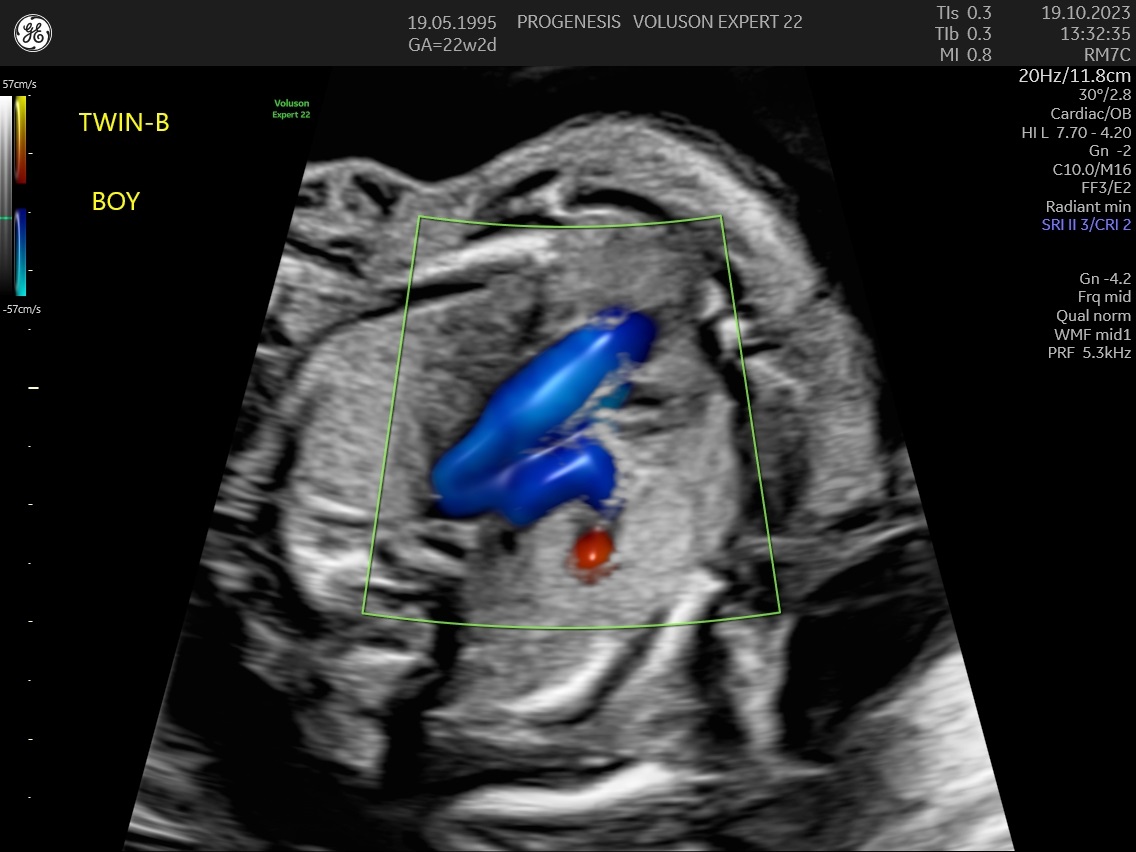

α) Η λεπτομερής αξιολόγηση της εμβρυϊκής ανατομίας, όπου αναγνωρίζονται τυχόν ανατομικές ανωμαλίες.

γ) Ο έλεγχος της ανάπτυξης του εμβρύου, του πλακούντα, του ομφαλίου λώρου και του αμνιακού υγρού.